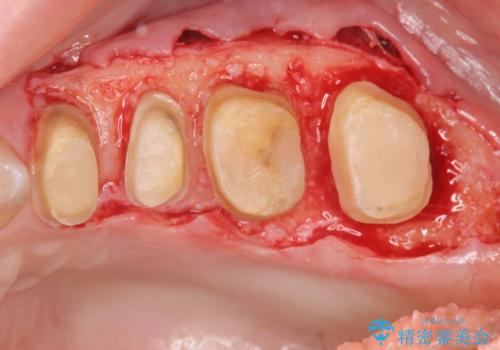

- 右上に装着されたブリッジのぐらつき、放置してしまった虫歯の治療を希望され来院されました。

ブリッジの支台、奥歯は虫歯や過大な咬合力により歯の破折・保存のできない大きな虫歯が認められます。

保存の難しい歯の抜去を行ったのち、咬合力にしっかりと耐えうる補綴設計としてブリッジや入れ歯ではなくインプラント治療を計画します。